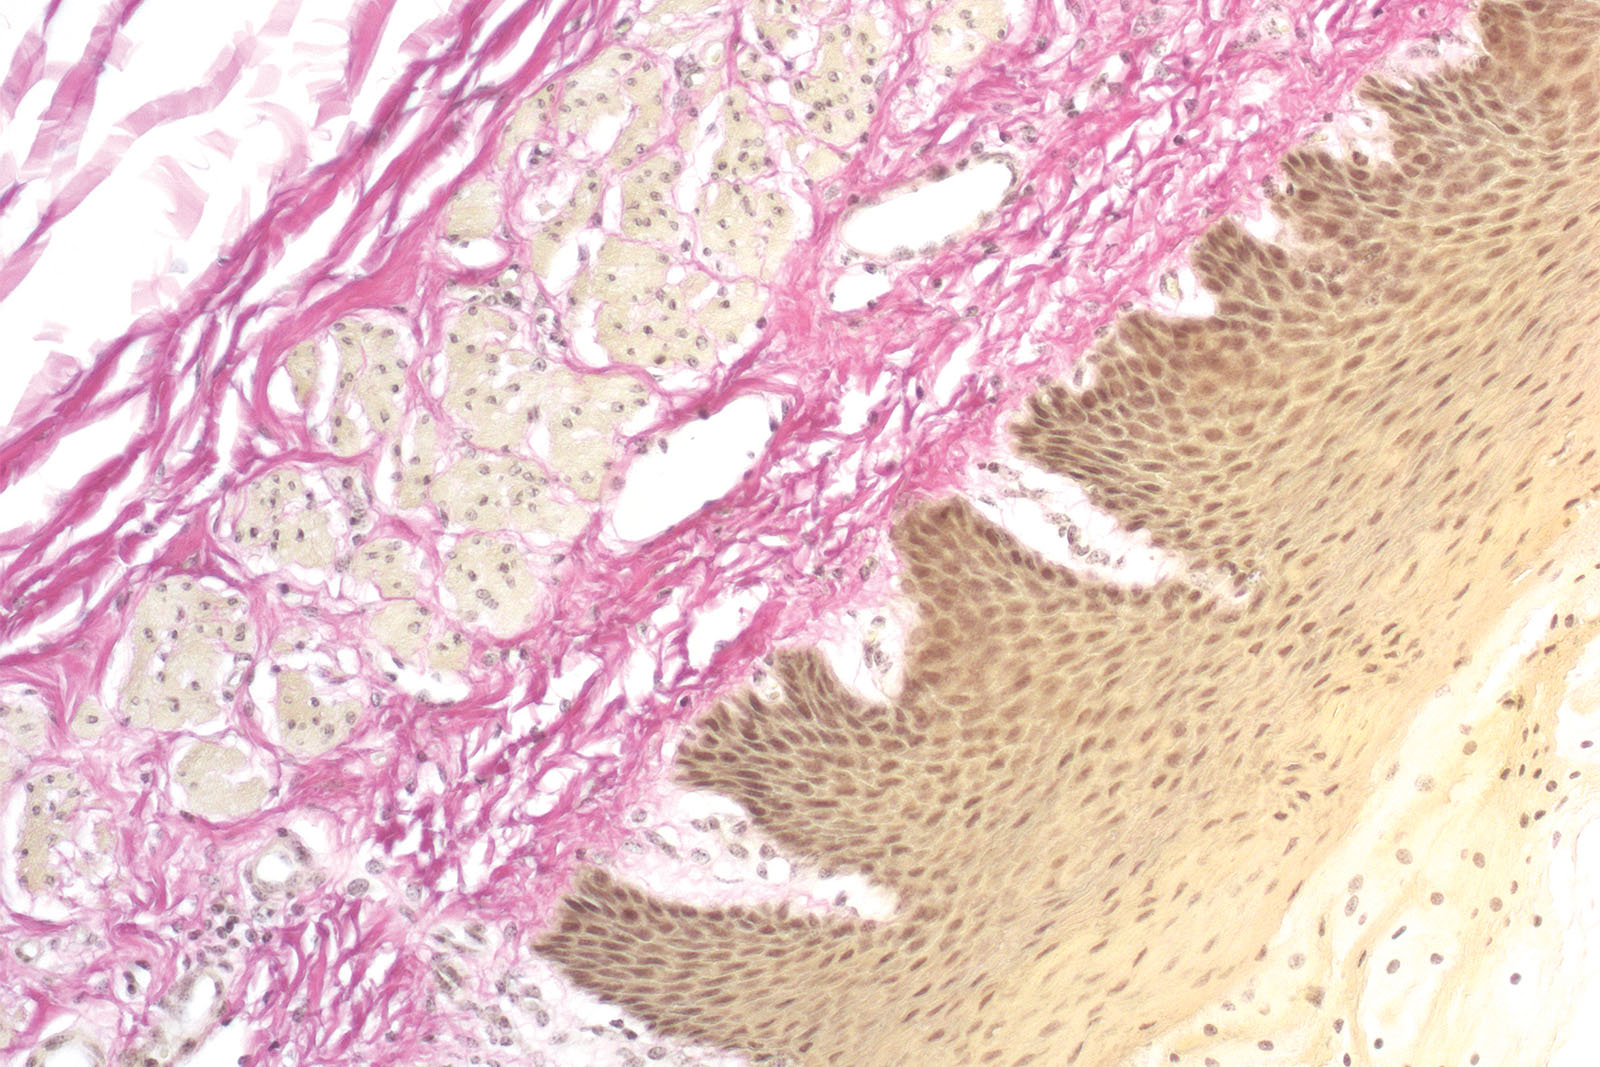

Il kit Van Gieson tricromica è utilizzato per la colorazione di collagene, tessuto muscolare, epitelio cheratinizzato, citoplasma, fibre gliali ed eritrociti. La fucsina acida Van Gieson è un componente del kit e contiene due coloranti (fucsina acida e acido picrico) che colorano contemporaneamente diverse strutture tissutali. La fucsina acida colora di rosso intenso le fibre di collagene, mentre l'acido picrico colora di giallo le fibre muscolari, gli eritrociti e le fibre gliali. Amiloidi, ialina, colloide e mucosa sono colorati con sfumature tra il rosso e il giallo. L'ematossilina, il Weigert A e il reagente ferrico costituiscono l'ematossilina Weigert che crea una colorazione stabile dei nuclei cellulari.

Risultati

Blu-marrone - nuclei

Rosso - collagene

Giallo - fibra muscolare, fibre gliali

Tonalità tra giallo e rosso - epitelio colloidale, mucoso, ialino, amiloide, cheratinizzato